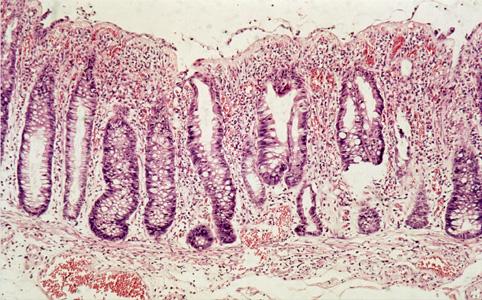

A case of cap polyposis in the rectum and sigmoid colon.

Inflammatory or ulcerative disease / lesions/Others

Large intestine(Colon)/Rectum

Histology

10 - 14